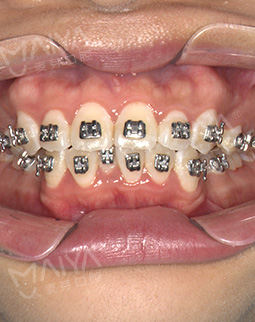

2017/03/17 矫正过程中

摘牙套前最后的一次拍照了,先看看牙,整齐啦!医生说等完全排齐后我就直接可以脱掉这些金属的东西了,想想好开心,吃盘龙虾奖励自己~~

2017/02/14 矫正过程中

欲速则不达!矫牙按部就班,医生说我排齐的不错,就是还有点咬合的问题,不过后期都是慢慢可以调整的,也是很nice了!另外托槽,皮筋,橡皮链这些如果掉了要及时去找医生黏贴好,如果你等到下次复诊再去,那么这段时间很有可能你的牙正在走弯路。也就延长你整牙时间了。